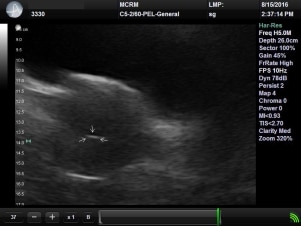

Fast forward to February; this was my first appointment with Dr. Nilson. I was excited! I had been diagnosed by my pervious Doctor with PCOS (Polycystic Ovarian Syndrome), but was hopeful about our next step. Dr. Nilson came in and we spoke and then he began an ultrasound. Within a few short minutes he explained that I didn’t have PCOS but instead had diminished ovarian reserve (DOR). He showed my husband and I that my left ovary had no eggs and my right showed three. He explained I would have bloodwork taken, that day, to look at my hormone levels. He called me a few days later, personally, and told me the news. As he spoke, his voice sounded like the teacher off Charlie Brown. He explained my AMH was .24. What I understood was I was well below the normal range for my age and with my follicle count at the day of my appointment, I didn’t have many eggs. He explained I needed to make a decision on whether or not to begin IVF (in vitro fertilization) and I needed to decide quickly as the odds were not in my favor. He suggested a facility in St. Louis, MCRM. I told him to send my information over and I would speak to my husband. I remember talking with my husband about it. It’s funny because he is always so calm, listens and is supportive, though this night; I could see his head spinning… mine sure was. He asked me what I wanted to do and the decision was easy… “We are doing IVF.” I never thought I would say though words.